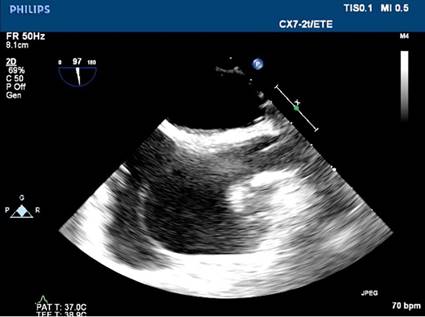

No se apreciaron colecciones ni abscesos. Se realizó una ecocardiografía transtorácica (ETT) en el servicio de urgencias, la que

suscitó sospechas de trombo/endocarditis. En la ecocardiografía transesofágica (ETE) posterior se comprobó la presencia de

un trombo adherido a los cables conductores del marcapasos. En las imágenes se

observó una vegetación dudosa. Se tomaron muestras de sangre para hemocultivo,

Después del tratamiento con HBPM durante una semana, se

produjo la resolución completa del trombo (Fig. 2).

Fig. 2. ETE: plano bicavo. Imagen de

los cables del marcapasos después de la anticoagulación; no hay evidencia de

trombo.